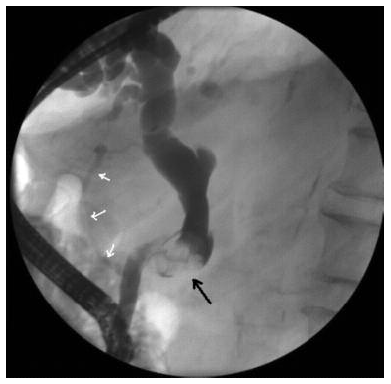

Endoscopic retrograde cholangiopancreatography is crucial to the evaluation of jaundice following liver transplant. We report a case of recurrent hepatocellular carcinoma 15 years after orthotopic liver transplant, presenting initially as obstructive bile duct compression as detected by cholangiogram(Figures 1 and 2). Laparotomy revealed hepatocellular carcinoma invading the common bile duct.

The physical examination was unremarkable except for icteric sclera. The patient’s laboratory values were as follows: total bilirubin level, 220.642 µmol/L (normal range, 5.0-21.0 µmol/L); alkaline phosphatase, 19.305 µkat/L (normal range, 0.5-2.0 µkat/L); aspartate aminotransferase, 5.318 µkat/L (normal range, 0.17-0.51 µkat/L); alanine aminotransferase, 6.296 µkat/L (normal range, 0.17-0.68 µkat/L); gamma-glutamyltransferase, 4.334 µkat/L (normal range, 0.03-0.51 µkat/L); and alpha fetoprotein, 36.8 µg/mL (normal range, 0-20 µg/mL). The results of a complete blood count were within normal limits. Computed tomography scanning revealed a 5.2 × 5.7 cm mass abutting the pancreas head (Figure 3). Endoscopic retrograde cholangiopancreatography showed an obstruction by the compressing mass at the level of the midportion of the common bile duct. This endoscopic retrograde cholangiopancreatography picture may have represented intraluminal invasion of the mass with no effect on the pancreatic duct (Figures 1 and 2). Fine-needle aspiration biopsy of the mass revealed malignant cells.

Although there have been previously reported cases in the literature, what is unique about the current case is the recurrence of hepatocellular carcinoma 15 years after liver transplant, causing obstructive jaundice in the absence of any mass effect in the liver parenchyma (1, 3, 4, 5). Another perspective of this case is its emphasis on the endoscopic retrograde cholangiopancreatography images that easily could have been misinterpreted initially as “bile duct stone disease.” Also, in the absence of mass effect in the liver parenchyma, a stone-related pathology was the initial diagnostic approach.